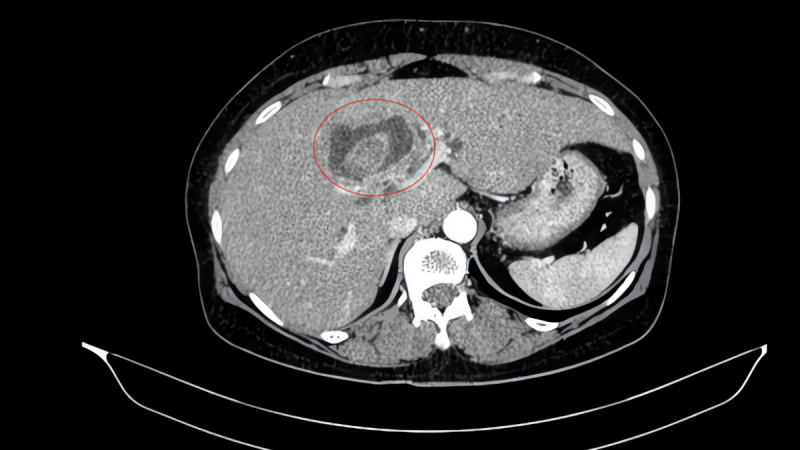

Bệnh nhân nữ, 59 tuổi, đi khám vì bị vàng da, ngứa và đau vùng hạ sườn phải kéo dài. Kết quả chẩn đoán hình ảnh cho thấy tổn thương đường mật trong gan kèm sỏi và giãn đường mật. Trong quá trình thăm khám toàn diện, nội soi tiêu hóa phát hiện thêm một khối u tại đại tràng lên.

Kết quả sinh thiết xác định đây là ung thư biểu mô tuyến. Sau hội chẩn đa chuyên khoa, các bác sĩ xác định bệnh nhân mắc đồng thời hai ung thư nguyên phát, thay vì một khối u di căn.

Cụ thể là bệnh ung thư đại tràng phải (giai đoạn sớm (IA), chưa di căn hạch) và ung thư đường mật trong gan (giai đoạn tiến triển (IIIB), có xâm lấn và di căn hạch).